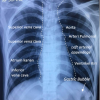

Dilakukan rontgen paru dengan hasil sebagai berikut.

Jika dilihat foto toraks terlampir, terdapat giant bullae pada paru kanan dan lesi infiltrat kedua lapang paru.